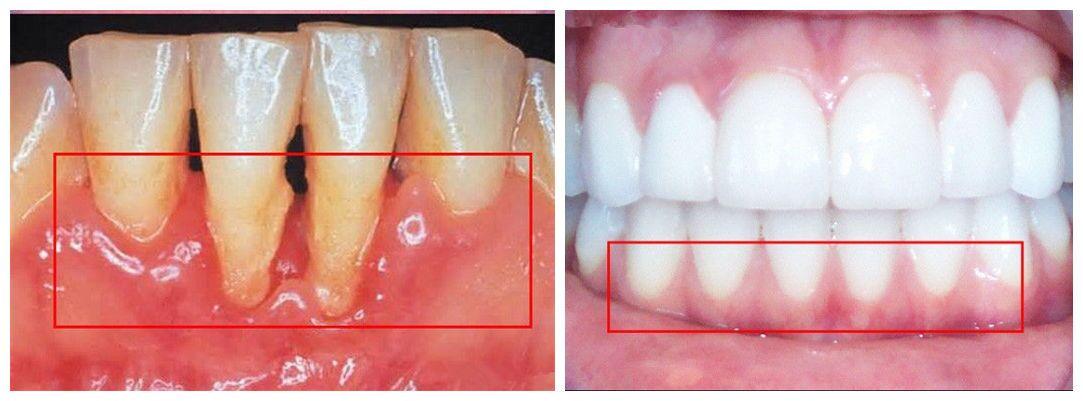

牙槽骨吸收,可能大家不明白是什么意思。通俗的来讲就是,牙槽骨因为牙周病变(例如炎症)等原因,发生了骨吸收的问题。这会使牙槽骨的骨量减少(变窄变矮),牙齿根部在牙槽骨的部分变短。

值得注意的是,牙槽骨吸收是一种不可逆的病变,通常通过治疗之后能够控制住现状就比较理想了。但也不排除少数人可能会自己恢复一些。

牙槽骨发生病变的初期,一般人难以感觉到。这就会让患者错过治疗的最佳时间。等病变发展到中期甚至后期的时候,患者口腔问题的处理都会变得比之前更加复杂。举三个例子: